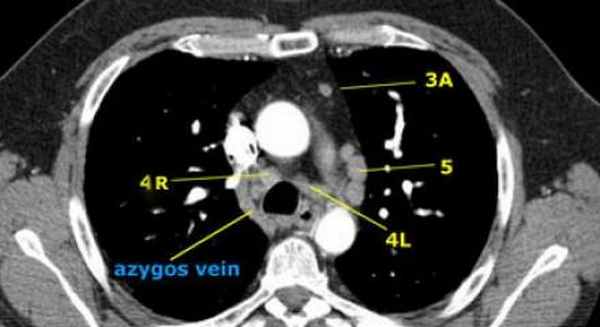

На изображении слева 3А узел в преваскулярном пространстве. Обратите внимание так же на ниже расположенные паратрахеальные узлы справа относящиеся к 4R группе.

4R. Правые нижние паратрахеальные лимфатические узлы

Верхняя граница: пересечение нижнего края левой плечеголовной вены с трахеей.

Нижняя граница: нижний края непарной вены.

4R узлы распространяются до левого края трахеи.

На изображении слева мы видим 4R паратрахеальные узлы. Кроме того здесь представлен узел кнаружи от дуги аорты, то есть 6 группы.

На левом изображении над уровнем легочного ствола представлены нижние паратрахеальные узлы слева и справа, так же здесь представлены узлы 3 и 5 групп.

Изображение слева выше уровня карины. Слева от трахеи 4L узлы. Обратите внимание что они расположены между легочным стволом и аортой, но не в аортопульмональном окне, потому что они лежат медиальнее артериальной связки. Лимфатические узлы латеральнее легочного ствола относятся к 5 группе.